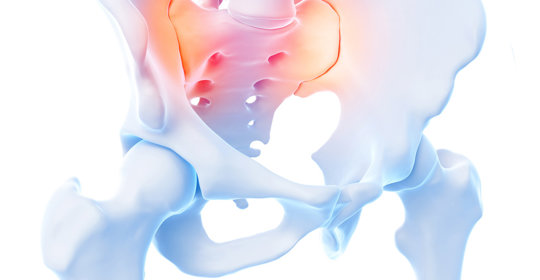

偏斜骨盆:原因和矯正方法

偏斜骨盆:就診科室、診斷方法、矯正措施

骨盆歪斜:骨科、脊柱外科、康復醫學科、物理治療科

偏斜骨盆:外擴、錯位、術後遺症及痛感管理

骨盆傷害:矯正方法與坐墊使用

偏斜骨盆:症狀與影響